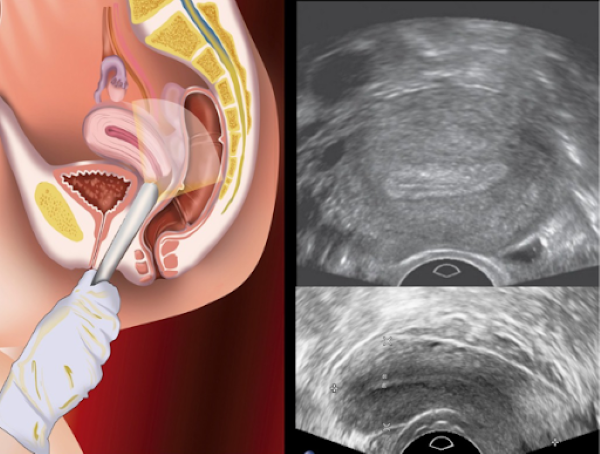

Siêu âm đầu dò âm đạo, hay còn gọi là siêu âm qua đường âm đạo, là phương pháp chẩn đoán hình phổ biến, có độ chính xác khá cao. Phương pháp này thường được chỉ định khi cần kiểm tra dấu hiệu bất thường ở tử cung, buồng trứng, cổ tử cung, vòi trứng, đánh giá tình hình rụng trứng và sự phát triển của trứng…

Siêu âm đầu dò có thể nhìn rõ nhất hình ảnh của buồng trứng đa nang trên siêu âm và cho kết quả chính xác cao hơn.

Trước khi được siêu âm đầu dò, chị em có thể được yêu cầu uống nhiều nước. Điều này có thể giúp bác sĩ nhìn rõ hình ảnh buồng trứng đa nang hơn. Sau đó, trong tư thế nằm dạng chân, bệnh nhân sẽ được luồn một đầu dò nhỏ qua âm đạo.

Các hình ảnh của buồng trứng sẽ được truyền tới màn hình và được chụp lại. Quá trình siêu âm đầu dò có thể kéo dài tới 30 – 60 phút.